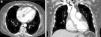

Pacemaker implantation for symptomatic bradycardia was proposed. During the fluoroscopy-guided transsubclavian vein positioning of the pacing leads, complete obstruction of the superior vena cava (SVC) was noticed, and the procedure was aborted. To elucidate the obstruction, a chest multidetector computed tomography (CT) scan was performed (BrightSpeed® 16 slice, GE Healthcare, Milwaukee, Wisconsin, USA) before and after intravenous contrast administration (120 ml of iopromide [Ultravist 370] at a rate of 3.5 ml/s) (Figure 1). Contrast-enhanced CT (non-ECG-gated) showed an infiltrative, hypoattenuating mass, apparently arising from the right atrium (RA) free wall and extending along the interatrial septum and epicardium, through the atrioventricular (AV) groove, following the course of the right coronary artery (RCA). No endoluminal arterial invasion was noted but the mass extended to the RA chamber, occluding the SVC. The mass showed no calcifications or necrosis, revealing mild enhancement. The proximal RCA was patent and a small pericardial effusion was observed.

Axial (a) and coronal reconstructed (b) images from non-ECG-gated enhanced computed tomography, at presentation. A primary cardiac lymphoma (asterisks, a, b) extends through the atrioventricular groove, the right atrial chamber and interatrial septum (asterisks). The patency of the right coronary artery (arrow, a) is preserved. A mild pericardial effusion is present (arrowhead, a) and superficial collateral circulation is shown (curved arrows, a). Coronal reconstructed images better illustrate the sparing of the aortic root (arrow, b) and obstruction of the superior vena cava (arrowhead, b).

A pronounced collateral circulation was evident along the thoracic wall, due to SVC obstruction. Based on the imaging findings the hypothesis of primary cardiac lymphoma (PCL) was proposed.